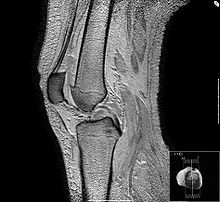

IRM du genou, coupe sagittale en écho de gradient pondération T2; mise en perspective du ligament croisé postérieur.